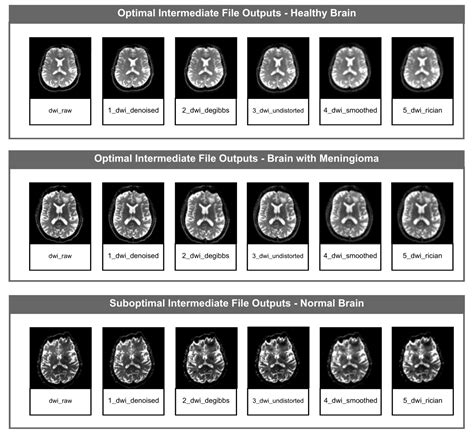

PyDesigner v1.0: A Pythonic Implementation of the DESIGNER Pipeline for ...

1358×1200